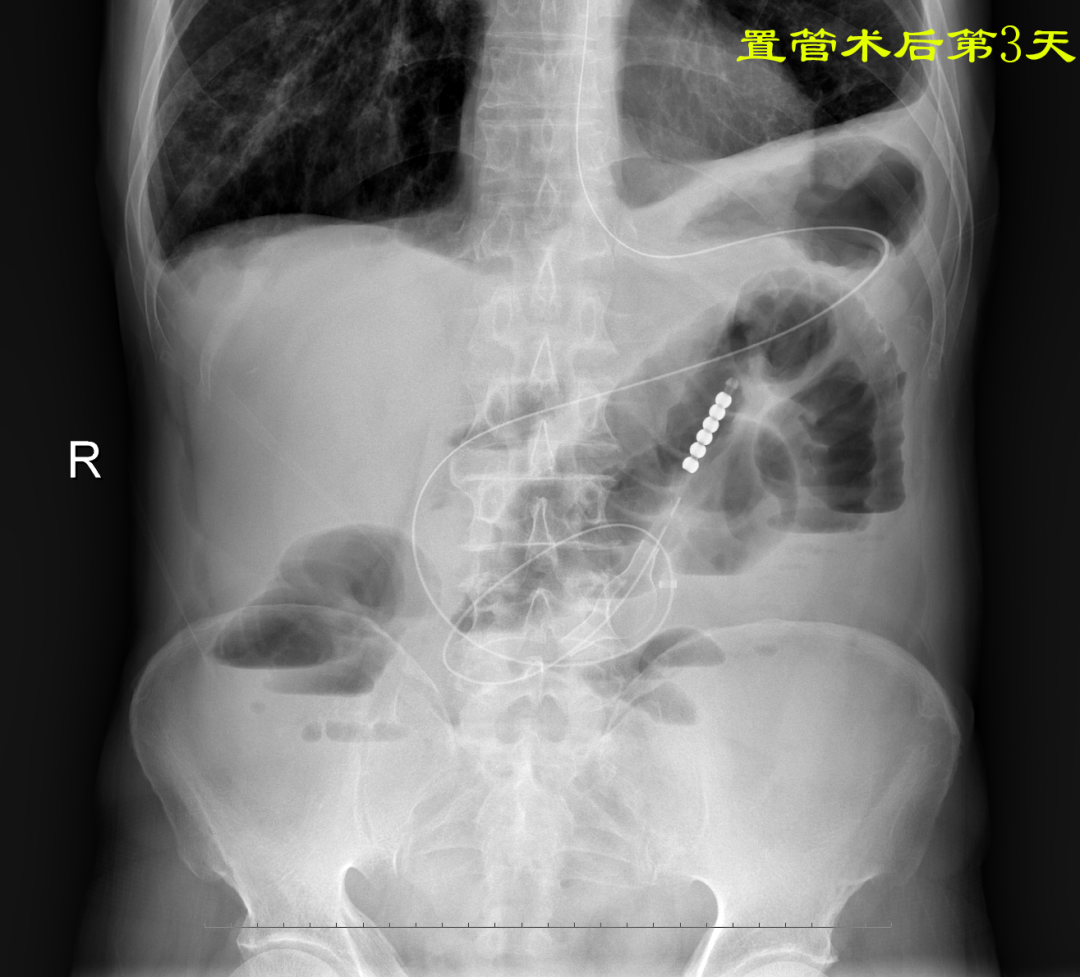

病例:患者男性,74岁,因“腹痛、腹胀伴呕吐、肛门停止排气排便20小时”于2021年7月24日入住我院普外科。患者1月前因回肠穿孔于我院普外科手术治疗,入院后明确诊断为术后粘连性小肠梗阻,经胃管引流等保守治疗无好转。因患者有严重心肺疾患,再次手术风险较大,并且术后再发粘连性肠梗阻的可能性也很大。经过与患者家属沟通后,最后决定采用胃镜引导下置入经鼻插入型肠梗阻导管技术来治疗肠梗阻。由我院消化内科副主任医师杨开余完成操作,耗时大约40分钟,患者术后第5天开始排气排便,腹痛、腹胀症状迅速消失,术后第7天拔除肠梗阻导管,恢复饮食。拔管至今已10天,患者已出院。随访患者无腹痛、腹胀,排便正常。

良好的引流是治疗肠梗阻的基本措施,低位小肠梗阻置入胃管引流常难以奏效,以往大多需要再次手术,而再次手术后粘连的几率高达70%。经鼻插入型肠梗阻导管就是将一根3米多长,内有四个腔道的管道置入十二指肠后,在重力和肠道蠕动的作用下,导管先端部将自动向前运动,直至到达梗阻部位。在导管到达梗阻部位后,可进行双对比造影检查了解狭窄病因,也可以对狭窄处进行扩张,还可以作为支架起到肠排列的治疗效果。肠梗阻导管治疗小肠梗阻属于微创型手术,具有痛苦小、疗效好、费用低、预防再次粘连等优点。

据悉,目前我省仅有为数不多的几家医院胃肠外科在开展此项技术,都是在C臂透视下经导丝置管,有X线暴露的缺点,我院现用胃镜辅助下置管可避免接触放射线。